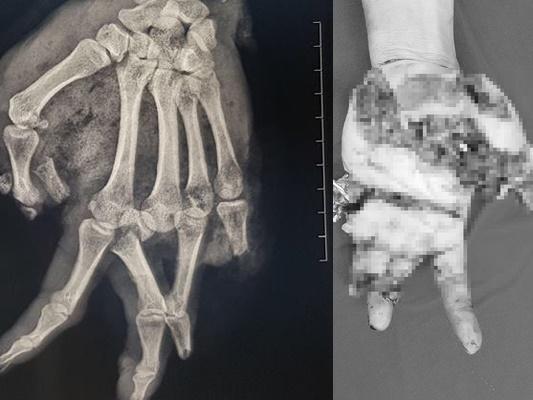

Bệnh nhân được sơ cứu tại bệnh viện địa phương trước khi chuyển lên Bệnh viện Tai mũi họng Trung ương. Tại đây, bệnh nhân được chẩn đoán mất thị lực hoàn toàn một mắt do vỡ nhãn cầu, mũi bị thương. Nguyên nhân dẫn đến tai nạn này là do nổ bình gas mini trong lúc nam thanh niên này đang nấu ăn.

Hiện, bệnh nhân đã được khâu nhãn cầu. Đồng thời khâu phục hồi vùng mũi, vết thương vùng mềm trên mặt, phục hồi chức năng thở, ngửi, thẩm mỹ cho bệnh nhân.